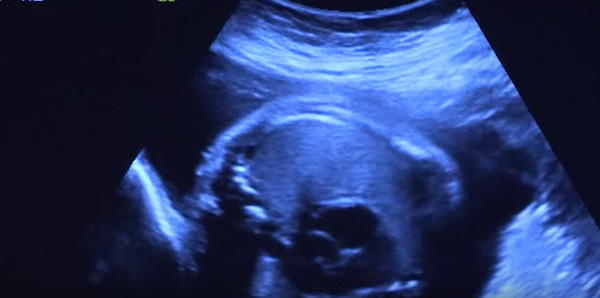

Thấy bụng có nhiều dấu hiệu bất thường, Guillermina đi khám và bất ngờ với kết quả siêu âm.

Tuy nhiên, không giống với những phụ nữ khác, sau khi có bầu một thời gian, cơ thể Guillermina bắt đầu có những thay đổi bất thường, bụng to nhanh như trương lên, trên da bụng của cô xuất hiện ngày càng nhiều những vết dạn, vết thâm và bầm tím. Lo lắng về những điều tồi tệ có thể xảy ra, Guillermina đã đến gặp bác sĩ để được tư vấn. Sau khi tiến hành kiểm tra và siêu âm, các bác sĩ đã vô cùng ngạc nhiên khi biết rằng trong bụng của cô có đến 5 thai nhi.

Bác sĩ Tracy Manuck cho biết những vết bầm tím trên bụng của Guillermina là do cô mang những 5 bào thai. Khi chúng cùng lớn dần lên khiến bụng cô to ra nhanh chóng, bụng mẹ quá chật chội nên chúng phải cử động nhiều để tranh giành không gian. Điều này làm cho bụng của Guillermina xuất hiện nhiều vết bầm tím.